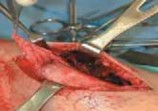

2. For a medially gapped Salter Harris type II abduction injury, a medial approach is used (

TECH FIG 1

).

A B CTECH FIG 1•

Surgical approach to a medially gapped fracture.

A.

This AP radiograph demonstrates a medially gapped Salter-Harris type II abduction-type fracture.

B.

A medial approach is used to obtain open reduction of this fracture.

C.

This operative photograph highlights the periosteum interposed in the physeal fracture, which was extracted to obtain anatomic reduction and prevent medial gapping.